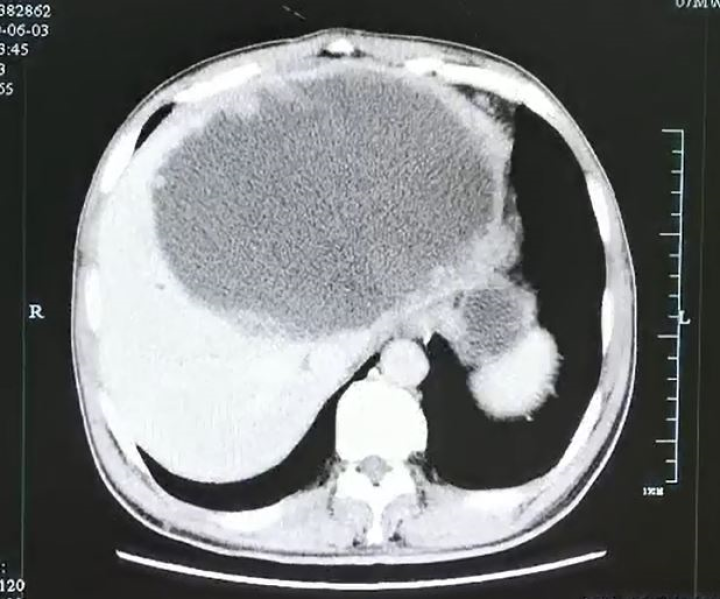

华支睾吸虫又称肝吸虫,是我国感染率最高的寄生虫之一,它可以寄生在人体的肝胆系统,产生毒素和一些分泌物,损伤肝细胞、胆管上皮细胞,引起肝脏反复的炎症、器官衰竭等症状,可能发展为肝硬化,严重时可能导致肝癌。